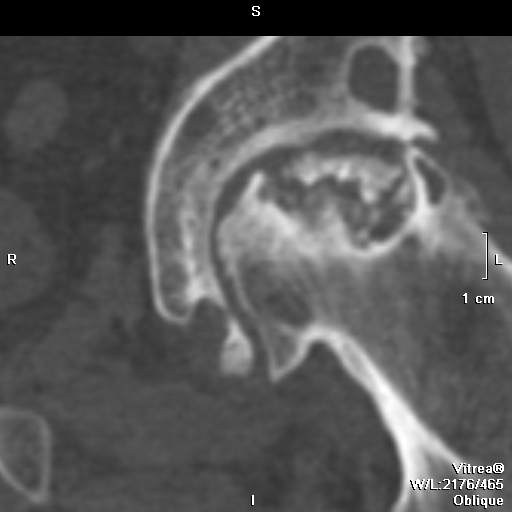

Диагностика ТБС рентгеном и асептический некроз: особенности лечения

Раздел: Снимки-откровения